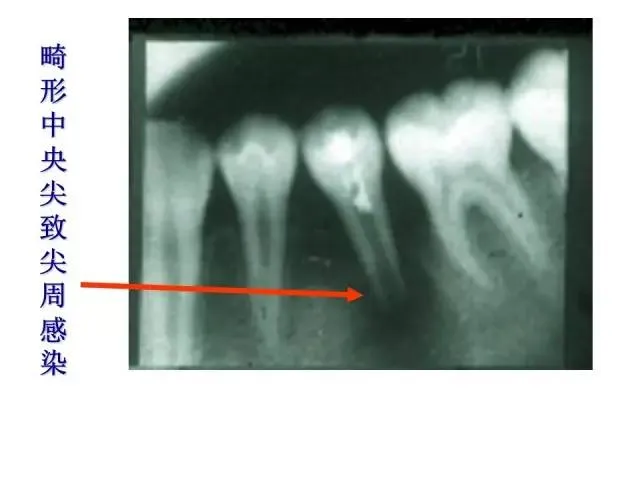

>PPT典藏 | 根尖诱导成型术